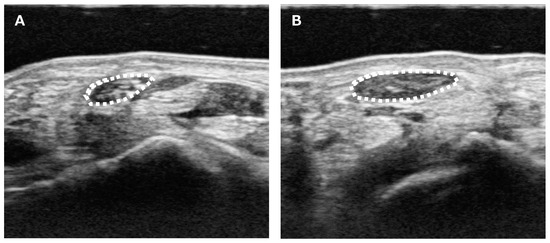

| Kim E, et al. (2015) [44] | A pilot study on ultrasonographic cross-sectional area of spinal nerve roots in cervical radiculopathy. The increased CSA of the affected nerve root compared to the unaffected side may be a useful, inexpensive, and simple supplementary clue for diagnosing cervical radiculopathy. |